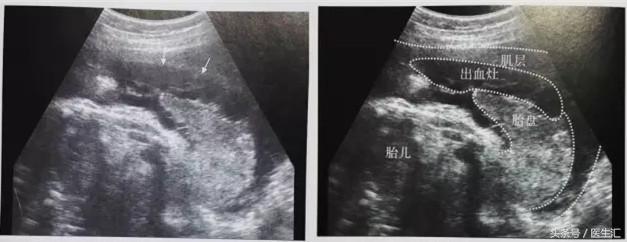

病例:女性,33岁,妊娠25+周,孕2产1,胎盘MR提示:胎盘后壁近宫底部分之胎盘后方见条带形异常信号,范围约72mm×18mm。

超声检查提示:宫底后壁胎盘与后壁肌层之间见混合回声区(超声表现1,见图1黄色圈内),与胎盘分界不清,范围约75mm×34mm,内回声不均匀,边缘及内部未见明显血流信号(检查要点1)。急诊剖宫产手术见胎盘80mm×50mm剥离面,占1/2(超过胎盘面积的1/3),宫腔积血约50ml,术后诊断胎盘早剥。

(图1)